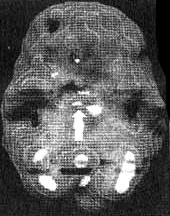

Мозг Эллен — последствия инсульта ![]() Трехмерное изображение поверхности мозга, вид слева. Обратите внимание на обширную «дыру», сформировавшуюся в результате инсульта в левой лобной доле 2. SPECT позволяет дать точную оценку состояния пациента, позволяющую предотвратить, заболевание в будущем. Нэнси, 59 лет, страдала от тяжелой депрессии, не поддававшейся лечению. Поступила в психиатрическую лечебницу, где ей было проведено исследование SРЕСТ. Каково же было мое удивление, когда оказалось, что в прошлом, при полном отсутствии соответствующих симптомов, она перенесла два обширных инсульта. Таким образом, стало понятно, что вызвало эту депрессию, не поддававшуюся обычному лечению. У 60 % пациентов, перенесших кровоизлияние во фронтальных долях, через год развивается тяжелая депрессия. Получив результаты SPECT, я немедленно проконсультировался с неврологом, который постарался определить причины инсультов, к которым нередко приводят, скажем, бляшки в сонных артериях или сердечная аритмия. Он пришел к выводу, что причиной инсультов у Нэнси стали тромбы, и назначил ей препараты, снижающие вязкость крови, чтобы предотвратить развитие новых инсультов. Мозг Нэнси — последствия двух инсультов ![]() Трехмерное изображение поверхности, вид сверху ![]() Трехмерное изображение поверхности, вид справа 3. С помощью SPECT можно получить информацию, помогающую врачу добиться понимания и сострадания к пациенту у членов его семьи. Фрэнк — состоятельный, хорошо образованный человек. Вскоре после того как ему исполнилось 70 лет, он стал забывчивым. Сначала он забывал мелочи, но со временем провалы в памяти стали прогрессировать, и он начал забывать значимые факты собственной биографии: где он живет, как зовут его жену и даже как зовут его самого. Жена и дети были не в состоянии понять, чем вызваны такие перемены, а его рассеянность и забывчивость их нередко раздражали. Результаты SPECT показали, что у Фрэнка на всей поверхности мозга отмечается резкое снижение активности, и особенно во фронтальных, париетальных и височных долях. Это была классическая картина синдрома Альцгеймера. Показав семье снимки и объяснив, что забывчивость Фрэнка имеет четкую физиологическую природу, я помог им осознать, что он не специально раздражает их, а серьезно болен. Впоследствии, вместо того чтобы упрекать его за забывчивость, близкие Фрэнка стали поддерживать его и разработали схемы, позволившие эффективнее бороться с трудностями, возникающими у всякого, кто вынужден жить рядом с человеком, страдающим болезнью Альцгеймера. Мозг Фрэнка — болезнь Альцгеймера ![]() Трехмерное изображение поверхности, вид сверху ![]() Трехмерное изображение нижней поверхности Обратите внимание на выраженное общее снижение активности, особенно в париетальных долях (см. стрелки, рис. слева) и в височных долях (см. стрелки, рис. справа). 4. SPECT позволяет проводить дифференциальную диагностику состояний со сходной симптоматикой. Я познакомился с Маргарет, когда ей было 68. Выглядела она неухоженно и неопрятно. Маргарет жила одна, и ее близких это очень беспокоило, так как у нее появились симптомы тяжелой деменции. После того как она чуть не сожгла дом, оставив включенной плиту, ее поместили в психиатрическую клинику, где в то время работал я. Из общения с ее близкими обнаружилось, что Маргарет часто забывала, как зовут ее собственных детей, и нередко, ведя машину, сбивалась с дороги и оказывалась в незнакомом месте. Водительские навыки ухудшились настолько, что после четырех небольших ДТП всёго за шесть месяцев у нее отобрали права. К тому времени, когда я встретился с ее близкими, многих из них эта ситуация уже утомила, и они были готовы сдать Маргарет в специализированный приют. Другие были против такого решения и хотели бы сначала обследовать ее в условиях стационара. На первый взгляд казалось, что Маргарет страдает болезнью Альцгеймера. Однако по результатам SPECT обнаружилось, что активность мозга в париетальных и височных долях не нарушена. Если бы у нее был синдром Альцгеймера, кровоток в этих областях должен был бы быть снижен. Вместо этого единственной патологией, которую нам удалось обнаружить на снимках SPECT, стала зона повышенной активности в глубокой лимбической области в центре мозга. Такая картина часто наблюдается у пациентов, страдающих депрессией. Из-за схожей симптоматики у больных старшего возраста нередко бывает трудно дифференцировать депрессию и болезнь Альцгеймера. Тем не менее при псевдодеменции (депрессии, которая выглядит как слабоумие) человек может выглядеть слабоумным, на самом деле таковым не являясь. Это чрезвычайно важный момент, так как, диагностировав болезнь Альцгеймера, мы даем близким ряд специальных рекомендаций и назначаем пациенту некоторые медикаментозные средства. Между тем, диагностируя депрессию, мы проводим агрессивную медикаментозную терапию антидепрессантами в сочетании с психотерапией. Результаты обследования Маргарет убедили меня в том, что ей следует назначить антидепрессант Wellbutrin (бупропион). Всего три недели спустя она уже была разговорчивой, ухоженной и охотно общалась с другими пациентами. Через месяц после госпитализации ее выписали домой. Перед выпиской она попросила меня написать письмо в автоинспекцию с просьбой вернуть ей водительские права. Поскольку мы с ней ездим по одному и тому же шоссе, я заколебался. Я сказал ей, что, если улучшение будет стойким и сохранится на протяжении по меньшей мере полугода, а сама она станет придерживаться рекомендаций врача и принимать все лекарства, я напишу письмо в автоинспекцию. Через полгода она оставалась в хорошей форме. Я сделал повторный SPECT — результаты показали полную норму. Тогда я обратился в автоинспекцию, и ей вернули права. Мозг Маргарет — псевдодеменция ![]() Трехмерное изображение снизу — активный мозг, до лечения. ![]() Трехмерное изображение снизу активный мозг, после лечения. |